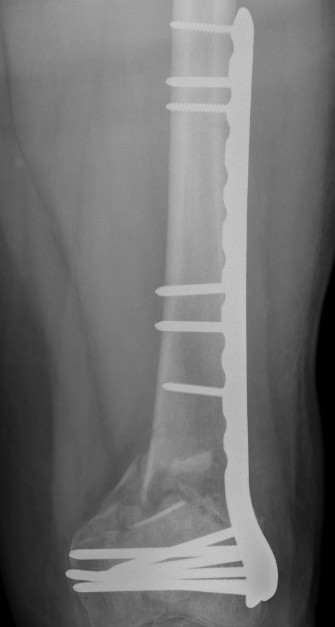

Xray

Lateral plate

Retrograde IM nail

Plate

Schutz et al Arch Orhop Traum Surg 2005

- 62 patients average age 52 years treated with LISS plate

- union achieved in 85% patients

- 6 required bone grafting, 3 required revision of components